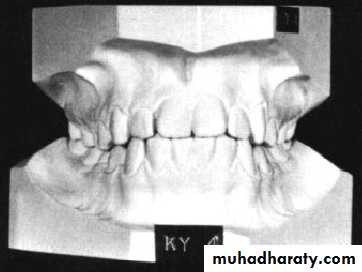

The Study model provides a three dimensional view of the maxillary and mandibular dental arches in all three planes of space,.i.e, sagittal, vertical and transverse planes.Model analysis allows us to carefully examine several parameters such as dentition, jaw relationships, and make objective measurements for detailed evaluation and treatment planning, also help in detecting midline discrepancies

the role of study cast at orthodontic treatment: 1. Record real teeth, alveolar bone, the palate and the base bone morphology and location. 2.Dentofacial deformity analysis conducted 3. Comparison in the course of treatment4. Compared the efficacy before and after treatment 5.One of the essential legal basis

Requisites of study models• Should accurately reproduce all the teeth and soft tissues without any distortion

• 2. Should be trimmed symmetrical on either side,so that the base of maxillary cast is trimmed parallel to the occlusal plan, upper and lower cast base should be parallel.

• 3. Posterior surface should be trimmed, such that when placed on their back they should reproduce the occlusal plane.

• 4. Should reproduce the alveolar process as much as possible.